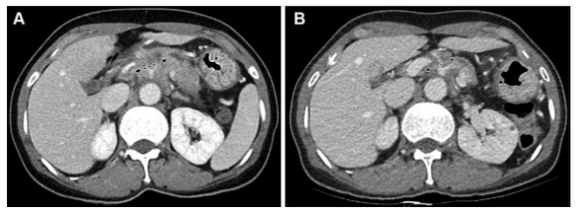

圖 一名54歲胰腺導管腺癌患者的圖像,為第一組的代表性病例(CT和CA 19-9反應者)。(A) 基線對比增強CT圖像顯示胰腺體部有一個30毫米的腫塊,腹腔動脈和肝總動脈被包圍(箭頭)。該腫塊為局部晚期可切除狀態(tài)?;€CA 19-9水平為391.9 U/ml。(B)使用5-氟尿嘧啶、亮丙瑞林、伊立替康和奧沙利鉑或FOLFIRINOX一線治療8周后獲得的后續(xù)對比增強CT圖像。由于腫塊的大小略微下降到27毫米(箭頭),根據(jù)實體瘤的反應評價標準,治療反應被歸類為疾病穩(wěn)定(CT反應者)。由于CA 19-9水平也降至29.2 U/mL,低于37 U/mL的臨界值,患者被歸類為CA 19-9反應者。沒有進行手術切除。在獲取數(shù)據(jù)時,該患者還存活,總生存期為44.7個月